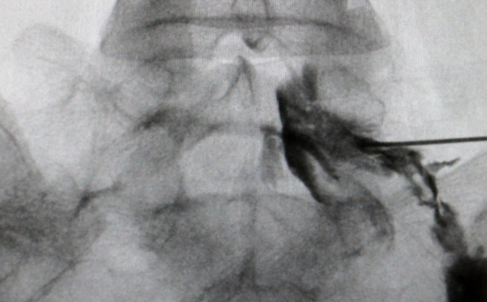

STEP3

약물주입